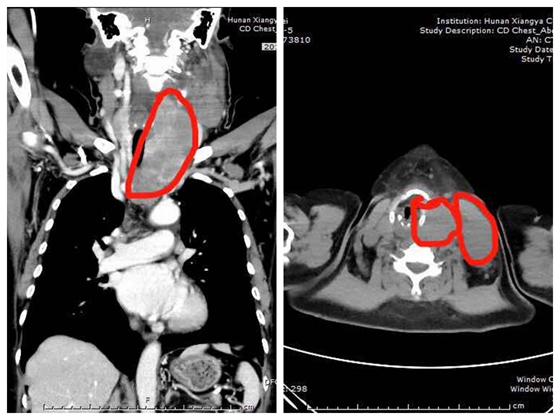

标记处为左侧甲状腺巨大肿块及左侧颈部多发肿大淋巴结

见到肖广发主任后,起初朱大妈不想拿出任何检查资料,她对肖主任说:“我现在只相信湘雅,我相信你们能行”。肖广发主任在仔细检查与查阅朱大妈既往的检查结果后,指出:患者甲状腺巨大肿块并颈部多发肿大淋巴结,考虑原发性甲状腺淋巴瘤可能,多次穿刺活检未能确诊;目前存在呼吸困难、吞咽困难、声嘶、活动障碍,手术是进一步解除压迫症状并明确诊断的最佳治疗方案

普外科肖广发主任主刀与团队行“双侧甲状腺全切+颈部淋巴结切除”,术中切除甲状腺肿物约10*200px,左侧颈部切除3个核桃大小肿大淋巴结,术中快速提示高疑淋巴瘤;手术过程中生命体征平稳,手术完成后等朱大妈呼吸顺畅,完全清醒后回到了病房。